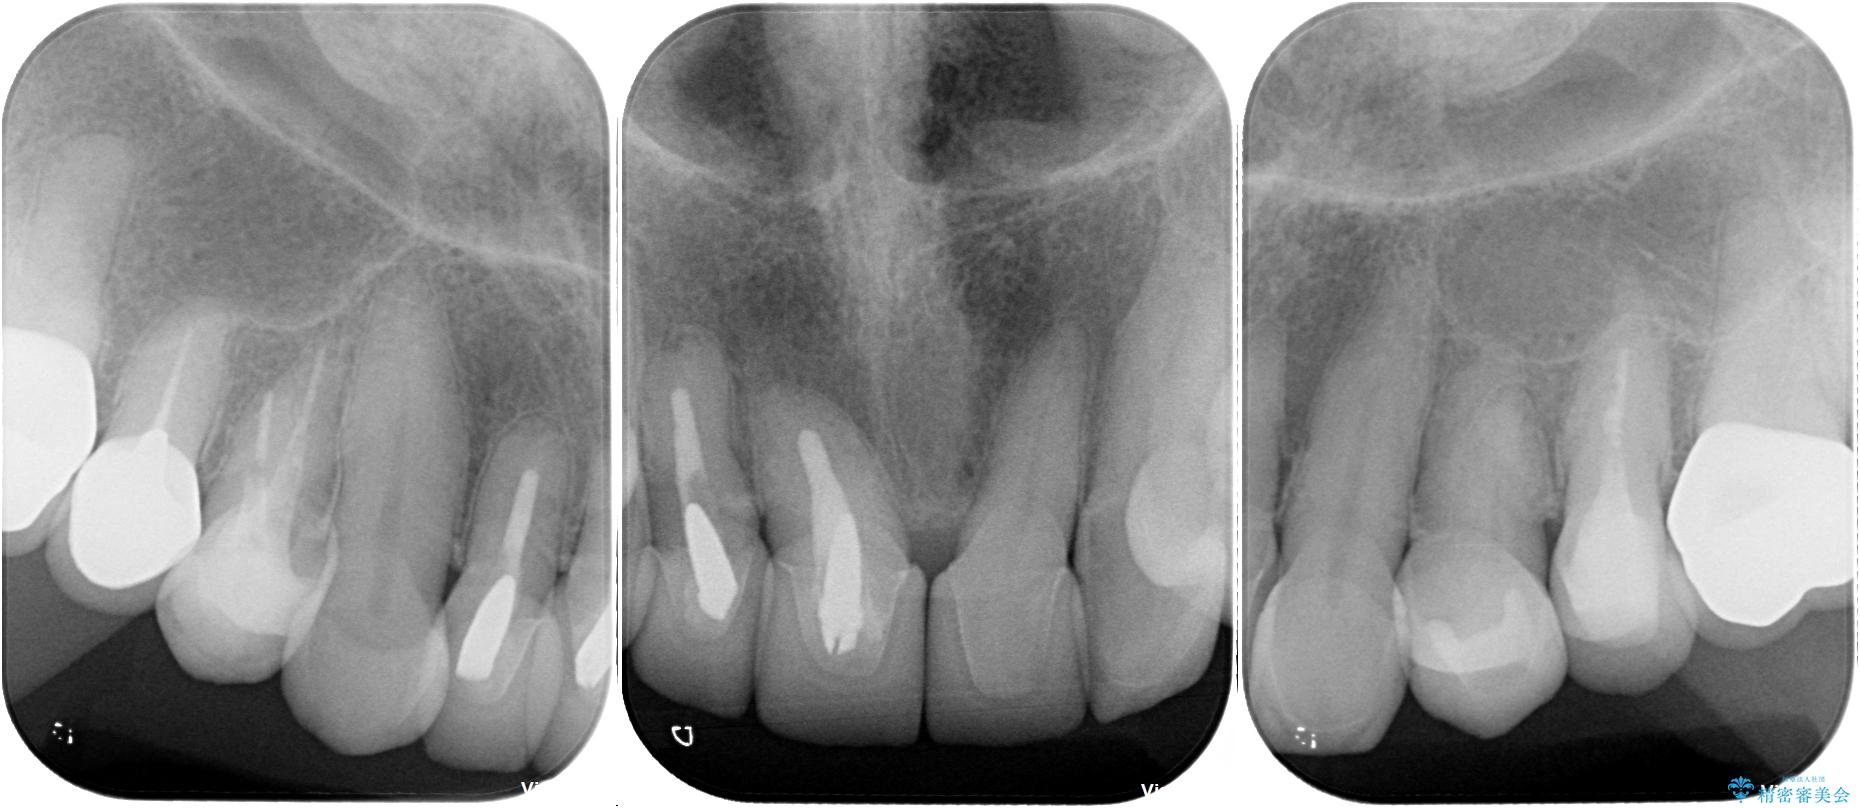

- 前歯のセラミックが欠けたり色調が不揃いであったりすることを気にして来院された患者様です。

20年以上前から、むし歯になったり詰め物が欠けたりする度に部分的に処置を行ってきたそうですが、この際統一感のある前歯にしたいとのことで、上顎前歯9本をオールセラミッククラウンによる補綴治療を行うこととしました。